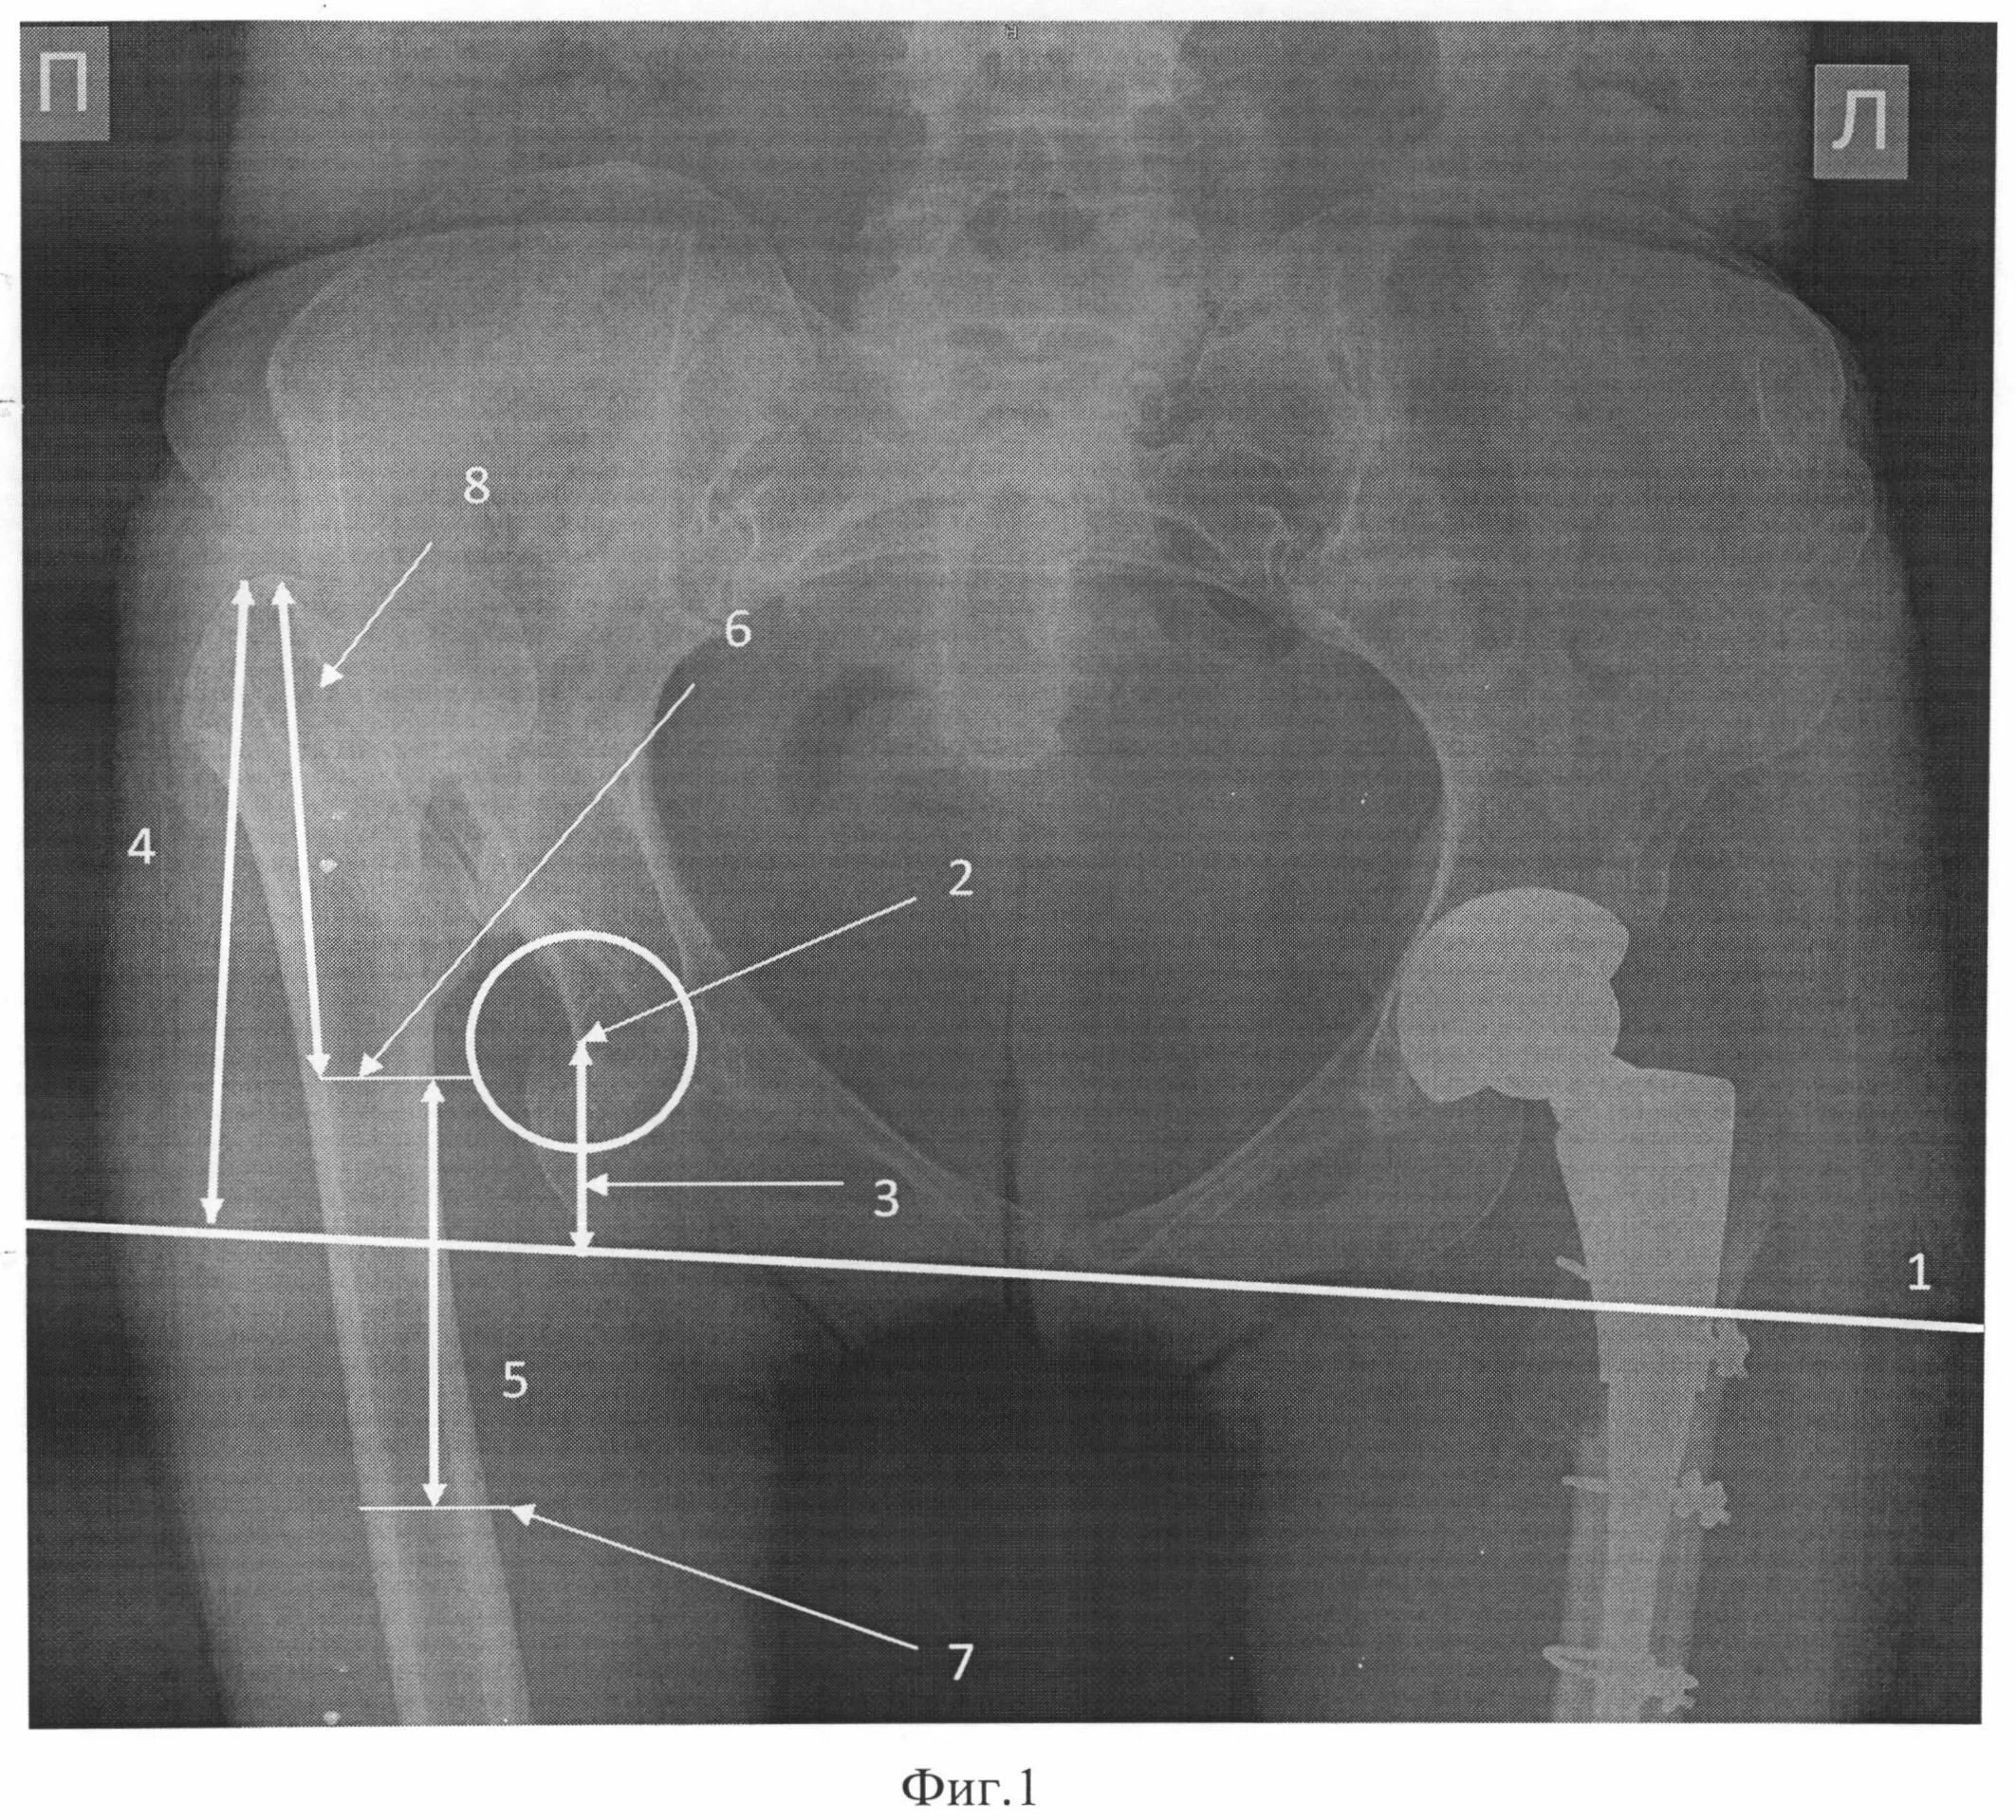

Обследование тазобедренного сустава